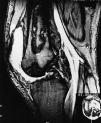

En junio de 1999 presenta dolor en articulación sin relación con el ejercicio, por lo que se realiza resonancia magnética nuclear (RMN), encontrándose los hallazgos radiológicos descritos en la fig. 1.

Figura 1. Cortes sagitales de rodilla derecha en secuencias potenciadas en T1 y T2. Imágenes de morfología irregular en región diáfiso-metafisaria del fémur compatibles con infartos óseos. Además se observan erosiones subcondrales sugestivas de necrosis avascular. Abundante derrame articular.

La RMN es la técnica no invasiva más sensible para el diagnóstico de necrosis avascular5. Los hallazgos más típicos fueron una o varias áreas de hiposeñal en la porción subcondral del cóndilo femoral y/o del platillo tibial en secuencias potenciadas en T1 y T2.

Estos hallazgos pueden encontrarse en tres tipos de pacientes: traumatismo previo, enfermedad predisponente (lupus, uso crónico de esteroides y trasplantados renales) y ancianos sin ninguno de los factores de riesgo descritos. Hay algunas diferencias en la osteonecrosis (ON) espontánea o primaria y aquella que se desarrolla en pacientes con factores de riesgo (ON secundaria). Así, en la ON de rodilla en aquellos pacientes con LES, trasplante renal o uso crónico de esteroides, la afectación es bilateral en el 50% y afecta al cóndilo lateral en el 60%. En la forma primaria la afectación es unilateral e incide en cóndilo femoral y platillo tibial mediales6.